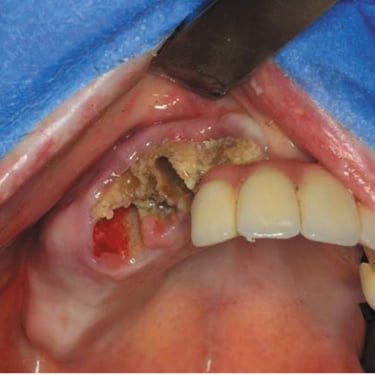

Absceso facial

Un absceso facial es una acumulación de pus en los tejidos faciales debido a una infección bacteriana.

Los pacientes pueden notar hinchazón, dolor intenso, fiebre y enrojecimiento en el área afectada.

El tratamiento incluye el drenaje quirúrgico del absceso y el uso de antibióticos para combatir la infección.